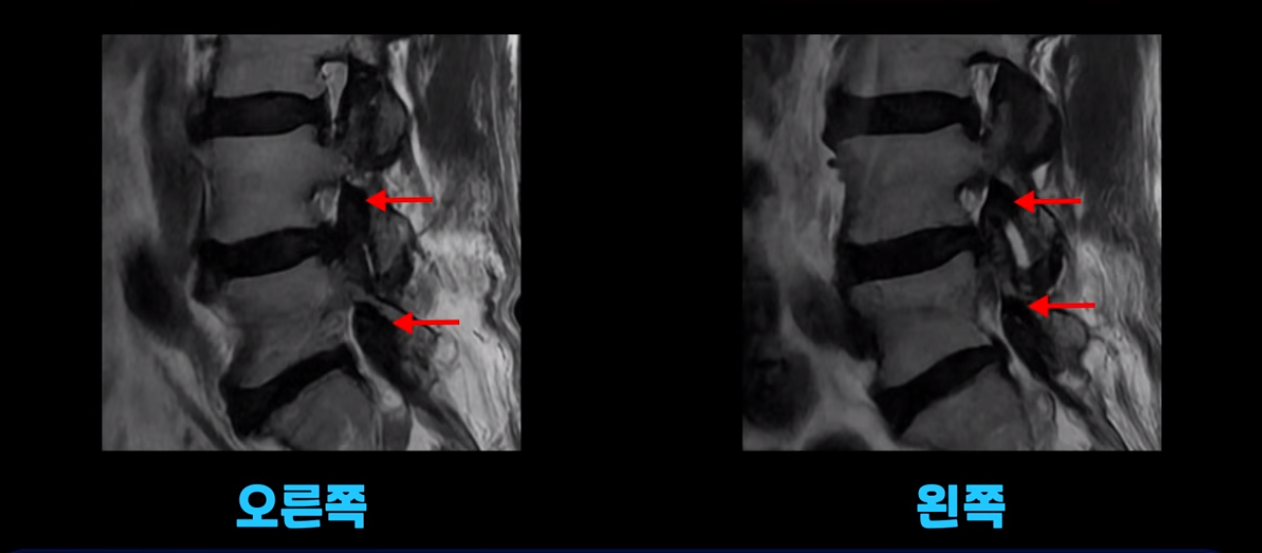

이분도 중증 근감소증 진단과 함께 척추기립근이 하얗게 지방으로 변한 것이 확인되었습니다. 당연히 허리, 엉덩이, 골반, 다리 근육들은 심하게 뭉치고 굳어있었습니다. 비슷한 증상의 환자분 이야기를 더 들어보겠습니다.

이 환자분 역시 근감소증 진단을 받으셨고, 척추기립근이 심하게 지방으로 변한 게 확인됩니다. 역시 허리, 골반, 다리 근육들은 다 뭉치고 굳어있었습니다.